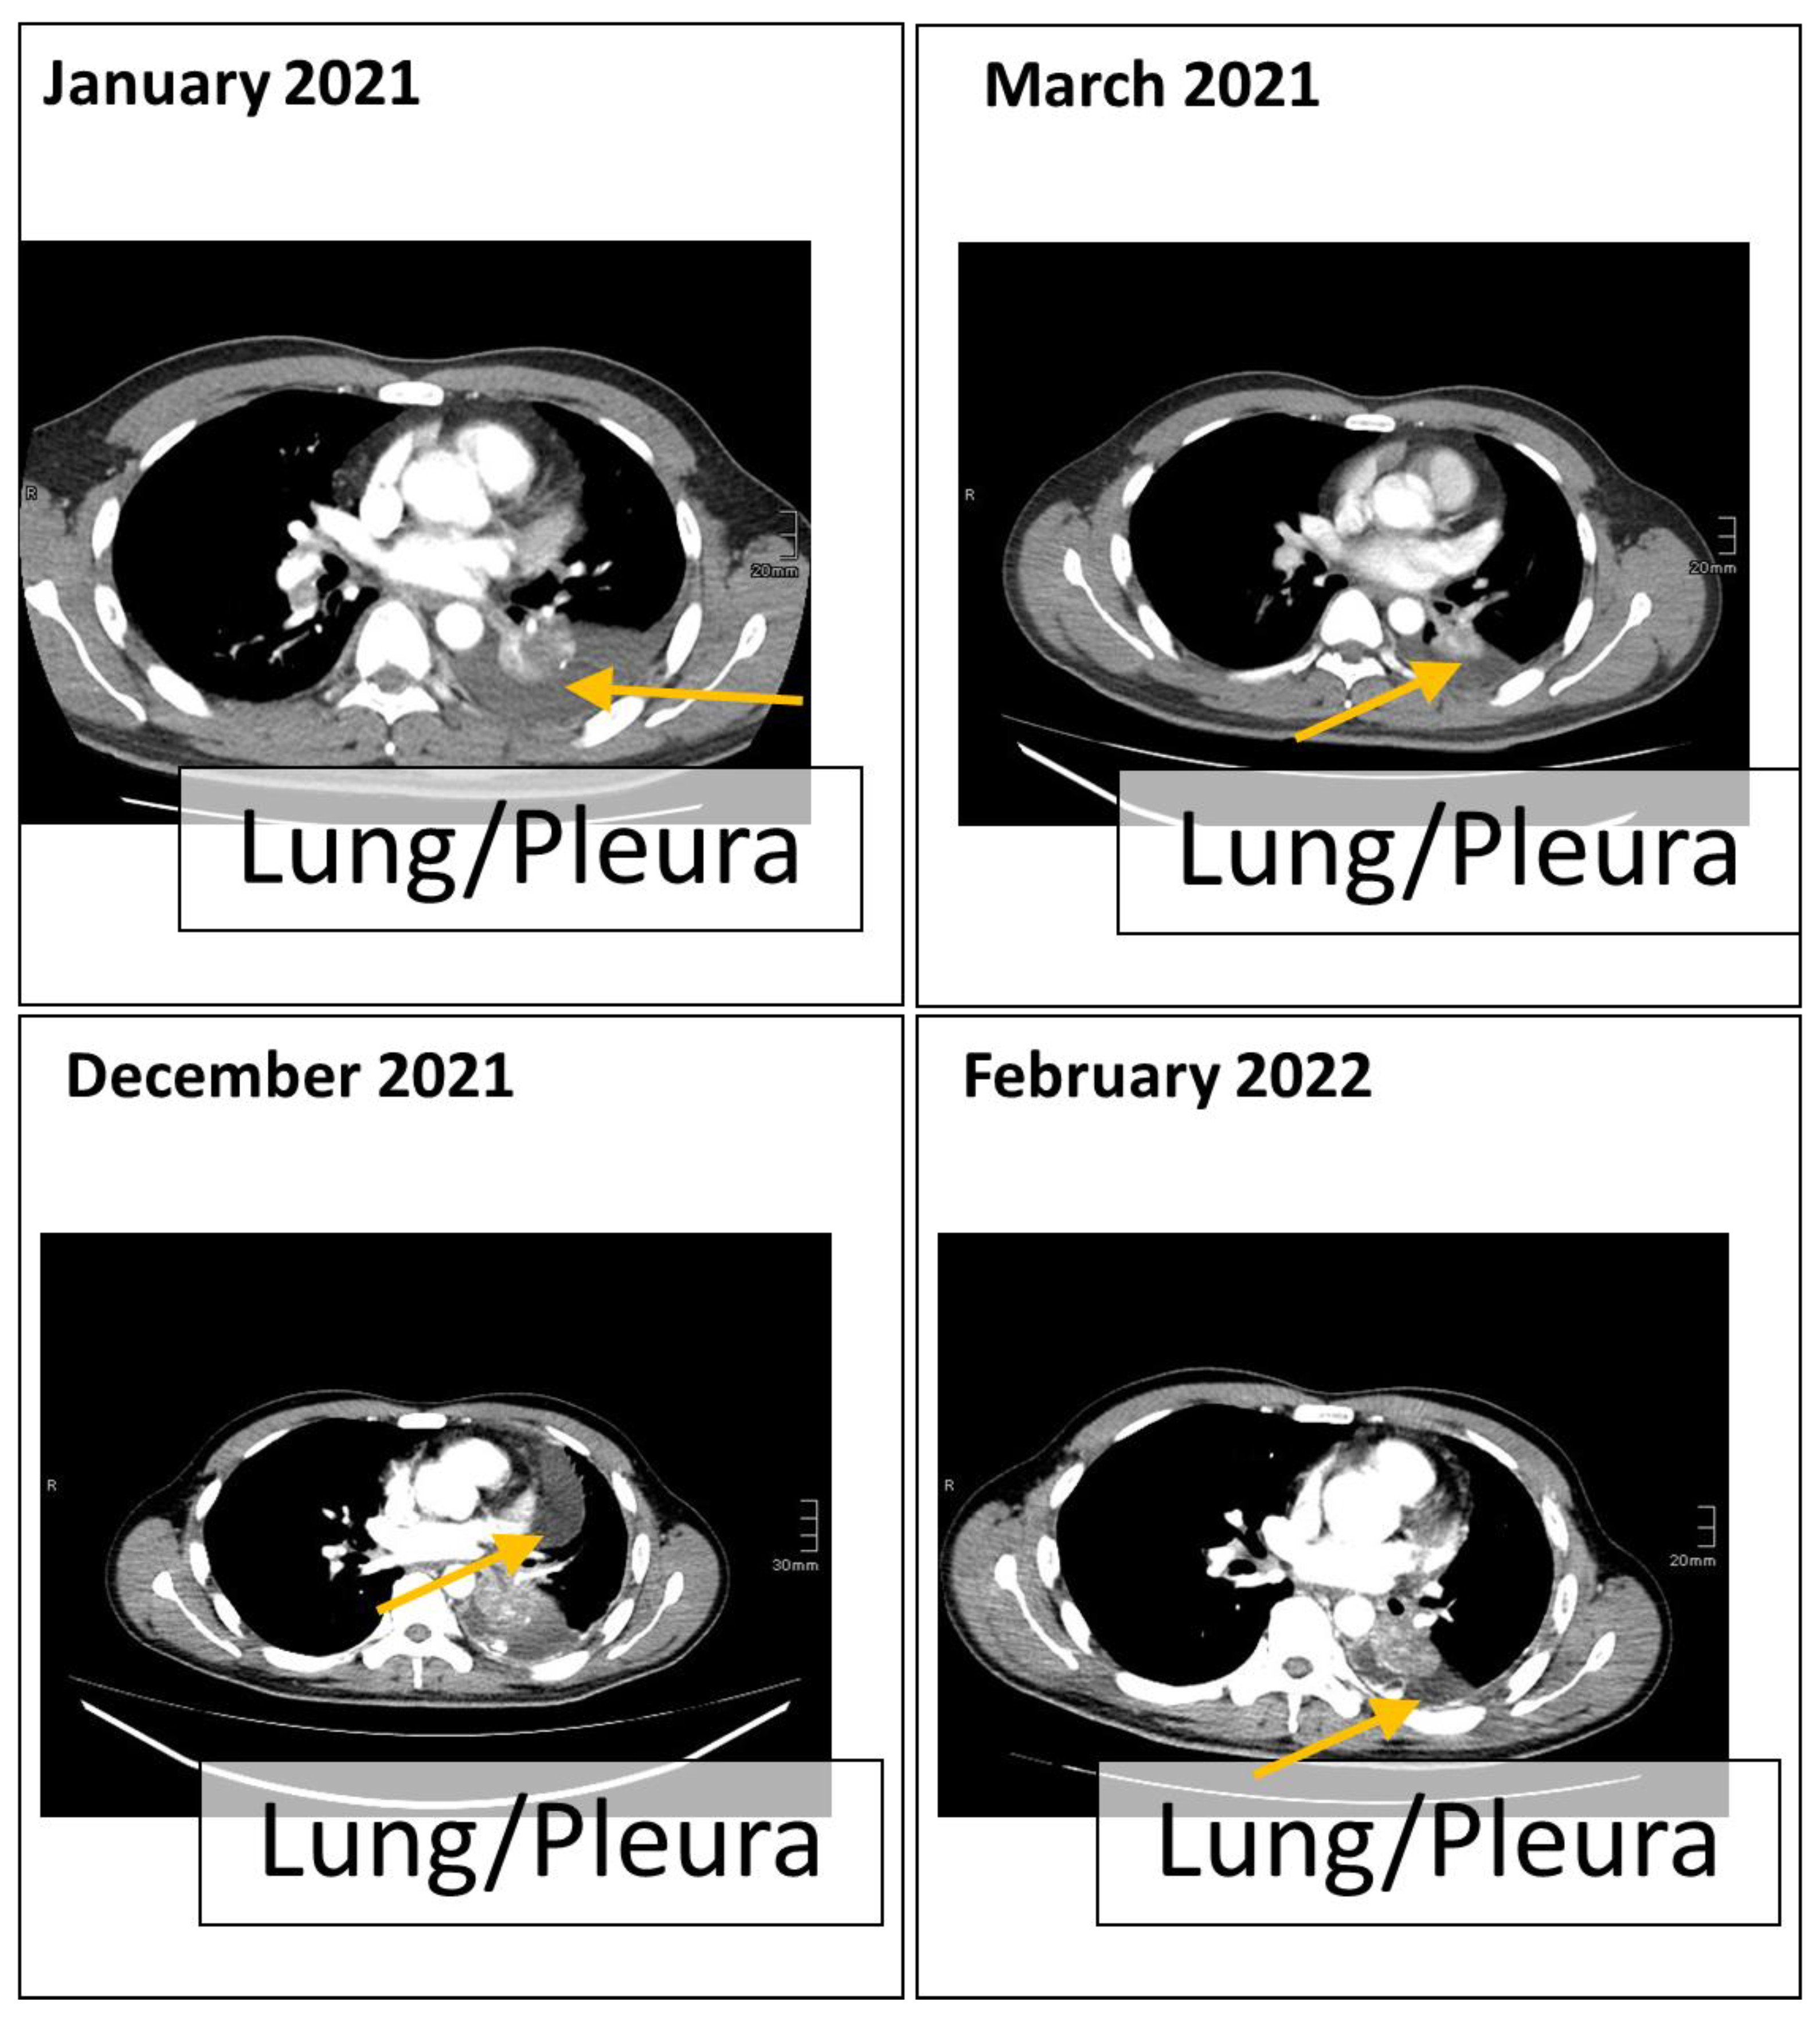

2. Case Presentation